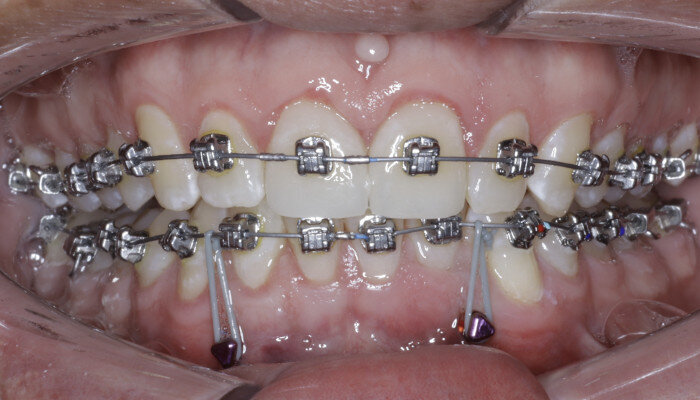

A great solution for Class III patients in need of mandibular distalisation for profile aesthetics and dental function is buccal shelf TADs. This solution allows for noncompliance correction of Class III cases with decreased compensation of the maxillary arch (Figs. 42–45, beginning of treatment). For these cases, a 2 × 12 mm Ortho Bone Screw is placed mesial to teeth #47 and #37 into the buccal shelf of the mandibular body. If the patient has mandibular third molars, then they are extracted right before the TADs are placed once in the stainless-steel wires.

Once the patient has progressed to stainless-steel wires, buccal shelf TADs are placed. A mandibular pre-posted stainless-steel wire is used, and a VectorTAS NiTi closing spring is placed from the buccal shelf TAD to the post (Fig. 46). Once the Class III has been corrected, a steel ligature is used to retain the Class III malocclusion while finishing and detailing are completed (Figs. 47–51, end of treatment).